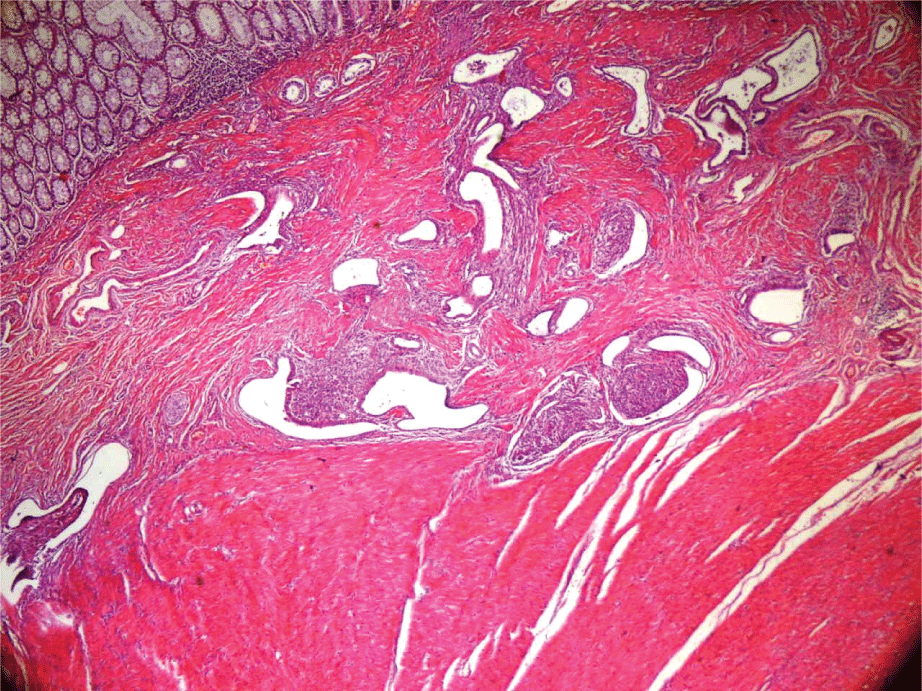

A 39-year old gravida 3 patient who presented with complaints of nausea, vomiting and no discharge of faeces or gas for 2 days was admitted to the emergency clinic with an initial diagnosis of ileus. The patient had previously been operated on for ovarian endometrioma at another clinic and was being followed up for pain associated with endometriosis. On the tomography image, a mass, 3.5-4.5cm in diameter, was observed in the recto-sigmoid region obliterating the lumen. In addition, proximal to this mass, the colon reached a diameter of 8cm. The preoperative haemogram and full urine test biochemistry values were examined. The patient was admitted for laparotomy and a colostomy was opened by resection from the recto-sigmoid region. In both ovaries, endometrioma of 5cm were observed, which had moved towards the Douglas pouch in the left ovary and widespread endometriotic foci were observed over the broad ligament attached to the Douglas pouch. A diagnosis of Grade 4 endometriosis was made [9]. As advanced stage endometriosis was determined in the patient, there was a history of endometrioma surgery and she was being followed up for pain, a total abdominal hysterectomy and bilateral oopherectomy were applied at the same session for definitive treatment. No problems were experienced in the postoperative period and the patient was discharged on the 7th day. The mass was causing a serosal adhesion and extending 3.5 x 3 x 3cm within the intestinal lumen at 25cm length and 10cm width. Microscopic images of the mass are shown in figures 1 and 2. The intestine was seen with transmural lumen involvement, showing frequent changes in the endometriotic tissue and atypical hyperplasia in focal areas. On the posterior surface of the uterus, focal endometriotic tissue was observed and findings were seen of endometrium delayed secretion. In accordance with the decision of the general surgeon, the colostomy was closed after 2 weeks and end-to-end anastomosis was applied.